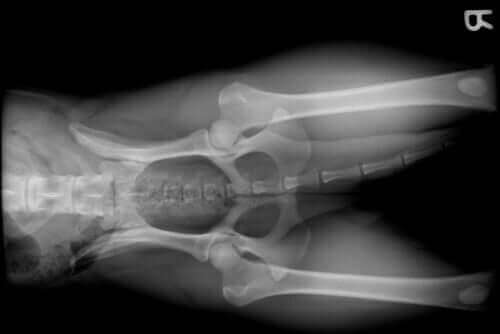

반려견에게 흔히 나타나는 질환 중 하나가 바로 관절 질환이다. 반려견이 다리를 절거나 급작스러운 통증을 호소하기 전까지는 보호자가 발병 여부를 알기 어렵다.

반려견의 관절 문제는 다음의 원인으로 발생할 수 있다.

- 견종: 저먼셰퍼드 같은 특정 견종은 고관절이형성증, 골든레트리버, 로트바일러와 도베르만 등의 대형 견종은 어깨와 팔꿈치 이형성증에 걸리기 쉽다

- 노견: 인간을 포함한 다른 포유류처럼 개도 나이가 들면 관절 퇴화 등의 변화가 관찰된다

- 성장 문제: 다른 종과 마찬가지로 개의 중요한 성장 기간에 영양 부족, 호르몬이나 품종 관련 문제로 관절 손상이 발생할 수 있다

- 골절: 관절 관련 골절 문제

- 전방 십자인대 부상: 과도한 운동, 과로 또는 반려견의 작은 체구 때문에 전방 십자인대 부상이 발생하면 심각한 관절 문제가 생길 수 있다

- 비만: 비만은 반려견 삶의 질을 낮추고 관절뿐만 아니라 다른 질환의 원인이 되기도 한다

- 관절증

- 관절염